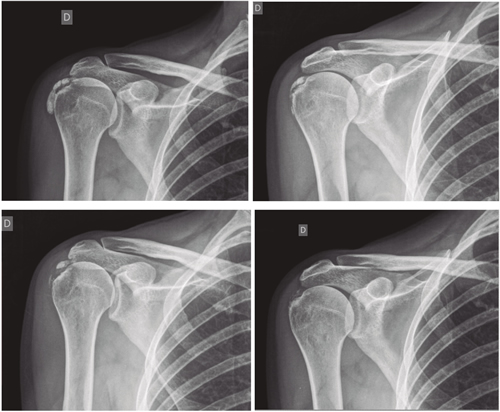

Figura 1

Figura 2

Tabla I

Figura 3

Figura 4

Figura 5

Figura 6